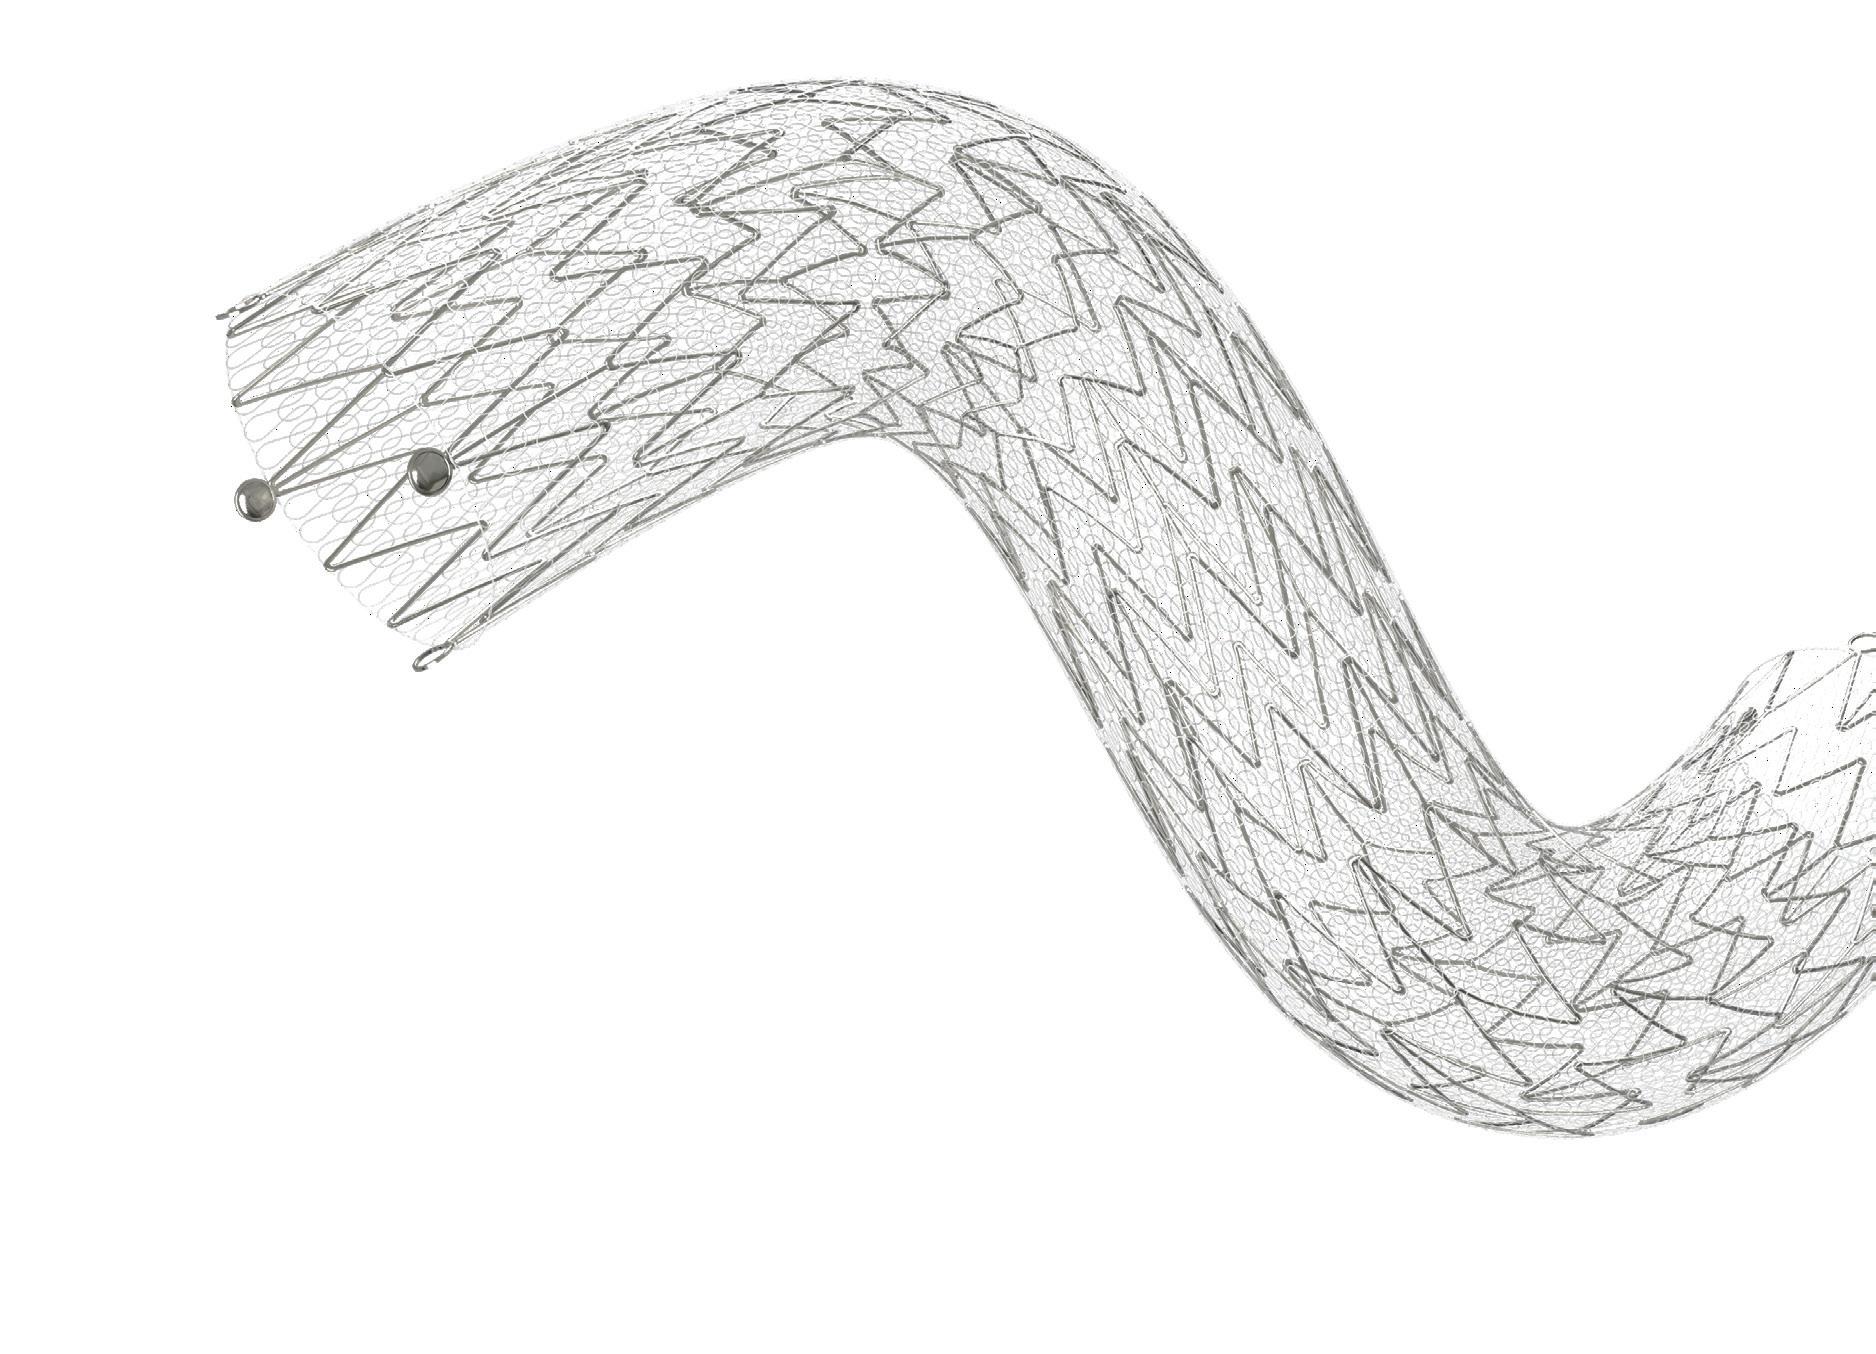

Following his presentation last year of 12-month results from the “landmark” LIFE-BTK randomised controlled trial, Ramon Varcoe (Sydney, Australia) speaks to Vascular News about this research as part of his wider career in vascular surgery so far. The vascular surgeon at Prince of Wales Hospital and full professor at the University of New South Wales also considers some of the biggest challenges currently facing the specialty, details his hobbies and interests outside of medicine, and reflects on how past experience in professional athletics has influenced his current work.

Why did you choose to pursue a career in medicine and what drew you to vascular surgery?

I come from a family with no history in medicine, so it surprised everyone when I chose that path at a young age. It’s hard to articulate why I was so strongly called to this career; sometimes, you just know things deep within.

Initially, I was drawn to psychiatry, which still fascinates me, but I ultimately prefer hands-on work, visualising anatomy in three dimensions, and solving problems. Vascular surgery, with its complex operations and the need to manage major blood vessels during critical moments, really appealed to me. At that time, the field was undergoing significant changes, shifting from traditional open surgery to an endovascular approach. I saw this as a perfect opportunity to be part of that transformation, where creativity and academic innovation were essential for advancing the specialty. I thrive in creative environments and have a passion for the scientific process.

Who were your career mentors and what was the best advice that they gave you?

I’ve had so many influential experiences that it’s tough to choose just a few. My earliest exposure to vascular surgery was with a pioneer in open surgery and transplantation in Sydney, John Frawley. He was a largerthan-life figure with a wealth of stories and an incredibly creative approach to surgery that was truly infectious. His inspiration shaped my early career.

In Adelaide, John Anderson was one of the early endovascular pioneers who demonstrated what’s possible when you think outside the box. At Westmead in Sydney, Professor John Fletcher became my first academic mentor, guiding me toward a lifelong passion for inquiry and a career in academia.

Geoff White, an endovascular aneurysm repair (EVAR) pioneer, and I collaborated on several conferences before his passing. The VERVE Symposium reflects much of what I learned while working alongside him. More recently, I’ve been fortunate to be mentored by Drs Michael Jaff and Peter Schneider, two giants in our field. They have both supported me and imparted invaluable lessons as my career has evolved.

What have been some of the most important developments in vascular surgery over the course of your career so far?

When I began my career in vascular surgery, it was primarily an open surgical specialty. EVAR was just emerging, and vascular

surgeons rarely performed peripheral endovascular interventions, especially complex ones. We had large, dedicated vascular wards filled with dozens of inpatients, many facing piecemeal amputations that often led to belowknee or above-knee amputations. Our intensive care units (ICUs) were crowded with vascular patients, and large-scale abdominal surgeries, particularly open abdominal aortic aneurysm (AAA) repairs, were routine, both elective and emergency.

That landscape has changed dramatically. We now admit only a fraction of those patients, and major amputations are rare at our centre. We often feel out of place in the ICU since we’re there so infrequently. The endovascular revolution has significantly improved patient care. Now, over 90% of my patients are likely to receive an endovascular-first procedure, with very few needing open surgery. This shift is beneficial for both patients and the specialty as a whole.

What are the biggest challenges currently facing vascular surgery?

I believe the biggest challenge we face now is how to manage the future of open vascular surgery. There are several key issues to consider. First, how do we ensure high-quality training for our trainees when open surgeries are becoming less common? Procedures like open abdominal aortic repairs, thoracoabdominal repairs, and distal bypass surgeries come to mind as complex operations that require a high level of technical skill. Unfortunately, these surgeries are rarely performed in most contemporary practices, and when they are, they often represent the most challenging cases. This makes training increasingly difficult.

Moreover, senior surgeons may feel less confident in supervising these procedures if it’s been a while since they last performed them. Over time, this could lead to newly graduated surgeons having less experience, further exacerbating the issue.